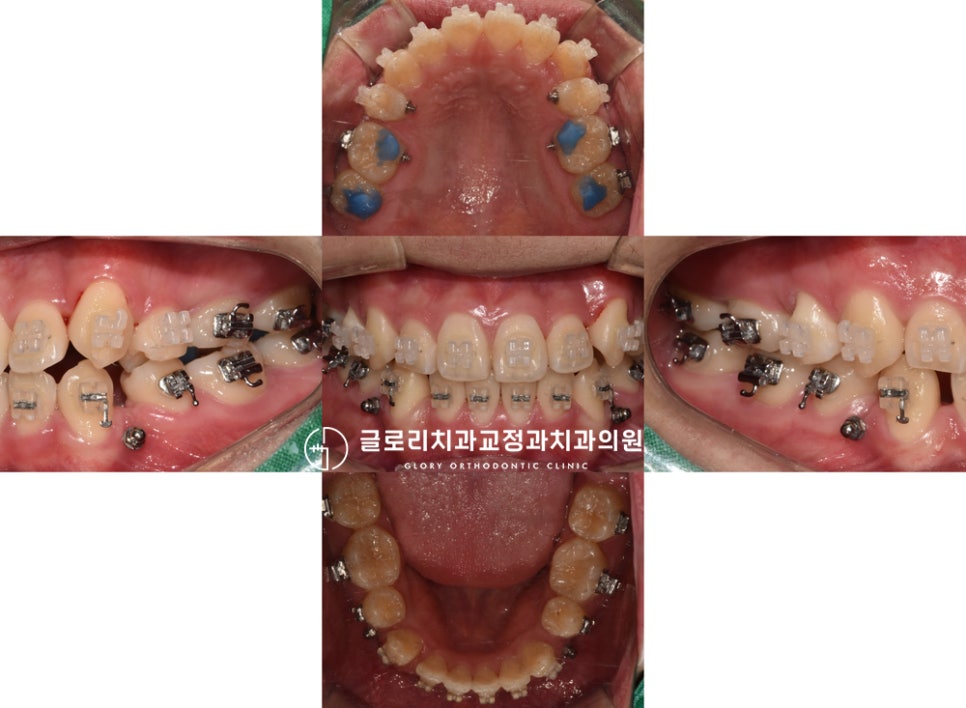

반대교합 및 덧니 개선 과정

거꾸로 물리는 반대교합과 덧니를 해결하기 위해

소구치 발치를 먼저 진행했습니다.

발치 후 이동을 이끌면서

올바른 교합을 완성시켜갔습니다.

이때 바이트블럭을 이용하여

교합을 의도적으로 띄워준 뒤,

전체 배열을 시행했는데요.

이때가 아마 제일 불편한 시기가 아닐까 싶습니다.

저희 망우역 치과 에서는 턱관절에

좋지 않은 영향을 주지 않게끔

치료 기간을 적절하게 조정하여 진행을 하고 있죠^^